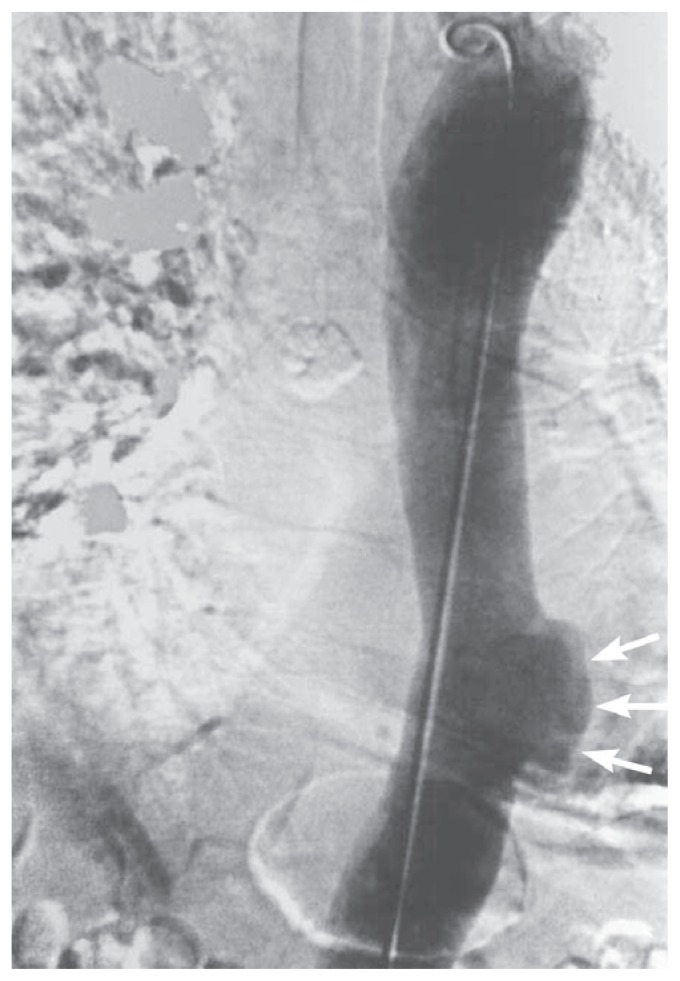

Penetrating atherosclerotic ulcer (PAU) is generally a less lethal condition than AAD and IMH (Figure 7).7 Patients can however, present with severe chest pain and require careful evaluation. More commonly however, PAUs are discovered incidentally on angiographic CT, or MRI imaging studies of the chest and abdomen that are performed for other indications (See Figure 8). They generally occur in densely calcified areas of atherosclerosis in the descending thoracic and abdominal aorta. A small percentage of the ulcers will progressively enlarge to form saccular aneurysms. They can also result in dissection and formation of an IMH. If surgical intervention is indicated for any of the above complications, endovascular repair is usually feasible if the ulcer is present in the ascending or abdominal aorta, and is preferred over open repair.

Figure 7.

Figure 8.